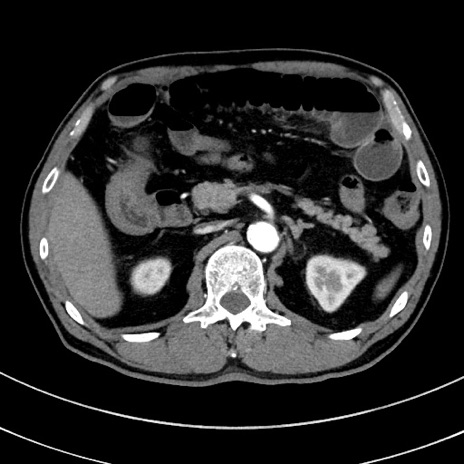

症例8(横断像)

【症例】 60歳代男性

【主訴】 黒色吐物

【現病歴】 4日前から嘔気自覚、2日前の朝食後にも嘔気あり、自分で手で嘔吐反射起こし嘔吐したところ血が混ざっていたため受診。

【既往歴】 5年前汎発性腹膜炎を伴う急性虫垂炎で手術、高血圧、前立腺肥大症、高脂血症

【身体所見】 腹部正中に手術癩痕あり 腹部平坦・軟圧痛なし膨満感あり

【データ】WBC 8400、CRP 4.54